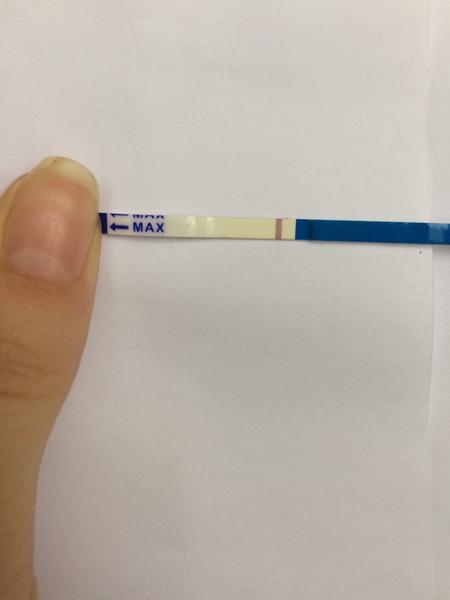

První byl ClearBlue a téměř hned tam naskočilo plus.

Udělal jsem radši ještě jeden - jmenuje se ForYou... Tam se objevil slabý duch, ale až tak za 3minuty! Šla jsem ven se psi a když jsem se vrátila, tak duch byl silnější...no ale to bylo skoro po půl hodině!

Tak nevim ... ☹ Dávám fotku, skuste posoudit...

- Slabá druhá čárka na domácím těhotenském testu může znamenat velmi časné těhotenství, biochemické těhotenství nebo vliv ředění moči a různou citlivost testů; spolehlivější potvrzení poskytne opakované testování z první ranní moči a krevní odběr hCG.

A: Intenzita čárky závisí na koncentraci moči (nejkoncentrovanější je ranní moč), na množství barviva v konkrétním testu a na množství hCG v krvi; v diskuzi také zaznělo, že čárka může být slabá v časném těhotenství nebo při biochemickém těhotenství.

A: Několik příspěvků varovalo, že čtení výsledků mimo doporučený čas může ukázat „ducha“ vlivem zaschnutí nebo chemických reakcí; spolehlivý výsledek je ten uvedený v návodu testu v doporučeném časovém okně.